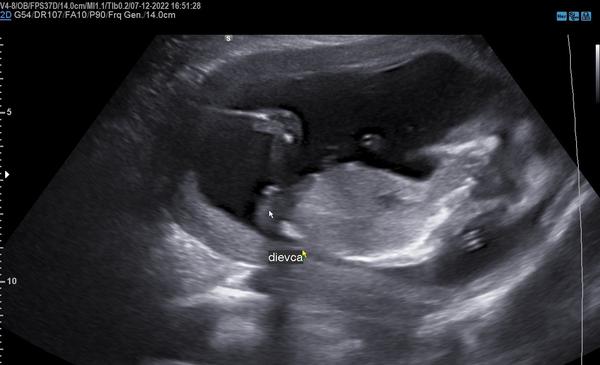

Dakujem dievcence. Eliska mala prist az 29.1. 2023 no rozhodla sa inak 🤷